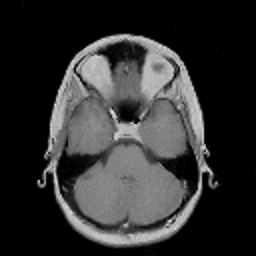

In this subsection, the MRI images from the built-in MRI dataset available in the MATLAB® toolbox have been used as test subjects. Specifically, the denosing algorithms have been tested using the axial slices number 4, 7 and 16 (shown in Figures 5, 5 and 5, respectively), which represent a spectrum of different cerebral structures. For quantitative comparison, simulated data have been obtained by subjecting the original test images to various levels of Rician noise.

Refer to caption

Figure 5: (a) Test slice #4, (b) Test slice #7 and (c) Test slice #16 of the MATLAB® MRI database.